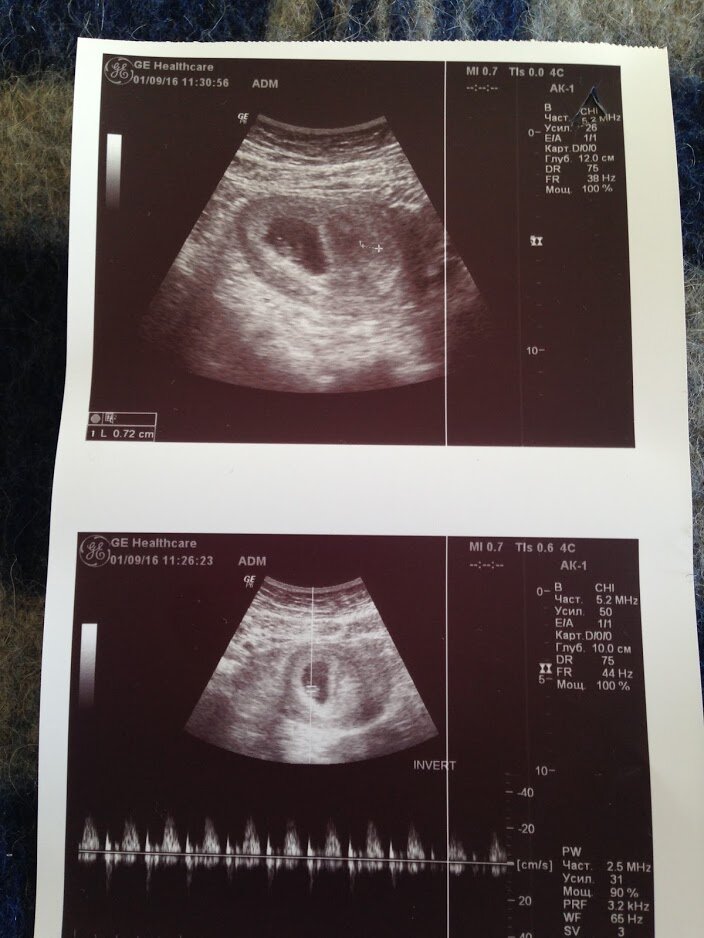

Отправили меня на УЗИ. Там сидел врач и еще молодая девочка интерн. И вот узист водит мне по животу этой штуковиной и говорит девочке интерну "вот матка, вот ее размеры, вот плод, в матке, вот его размеры, плод живой, прослушивается сердцебиение, а вот небольшое пятно это гематома, и еще тонус в матке..." Я лежу все это слушаю и чувствую себя какой то подопытной овечкой. Мне просто было сказано, что все хорошо, просто немного есть тонус и гематома. Это меня конечно окрылило, слава богу это обычная нормальная маточная беременность!